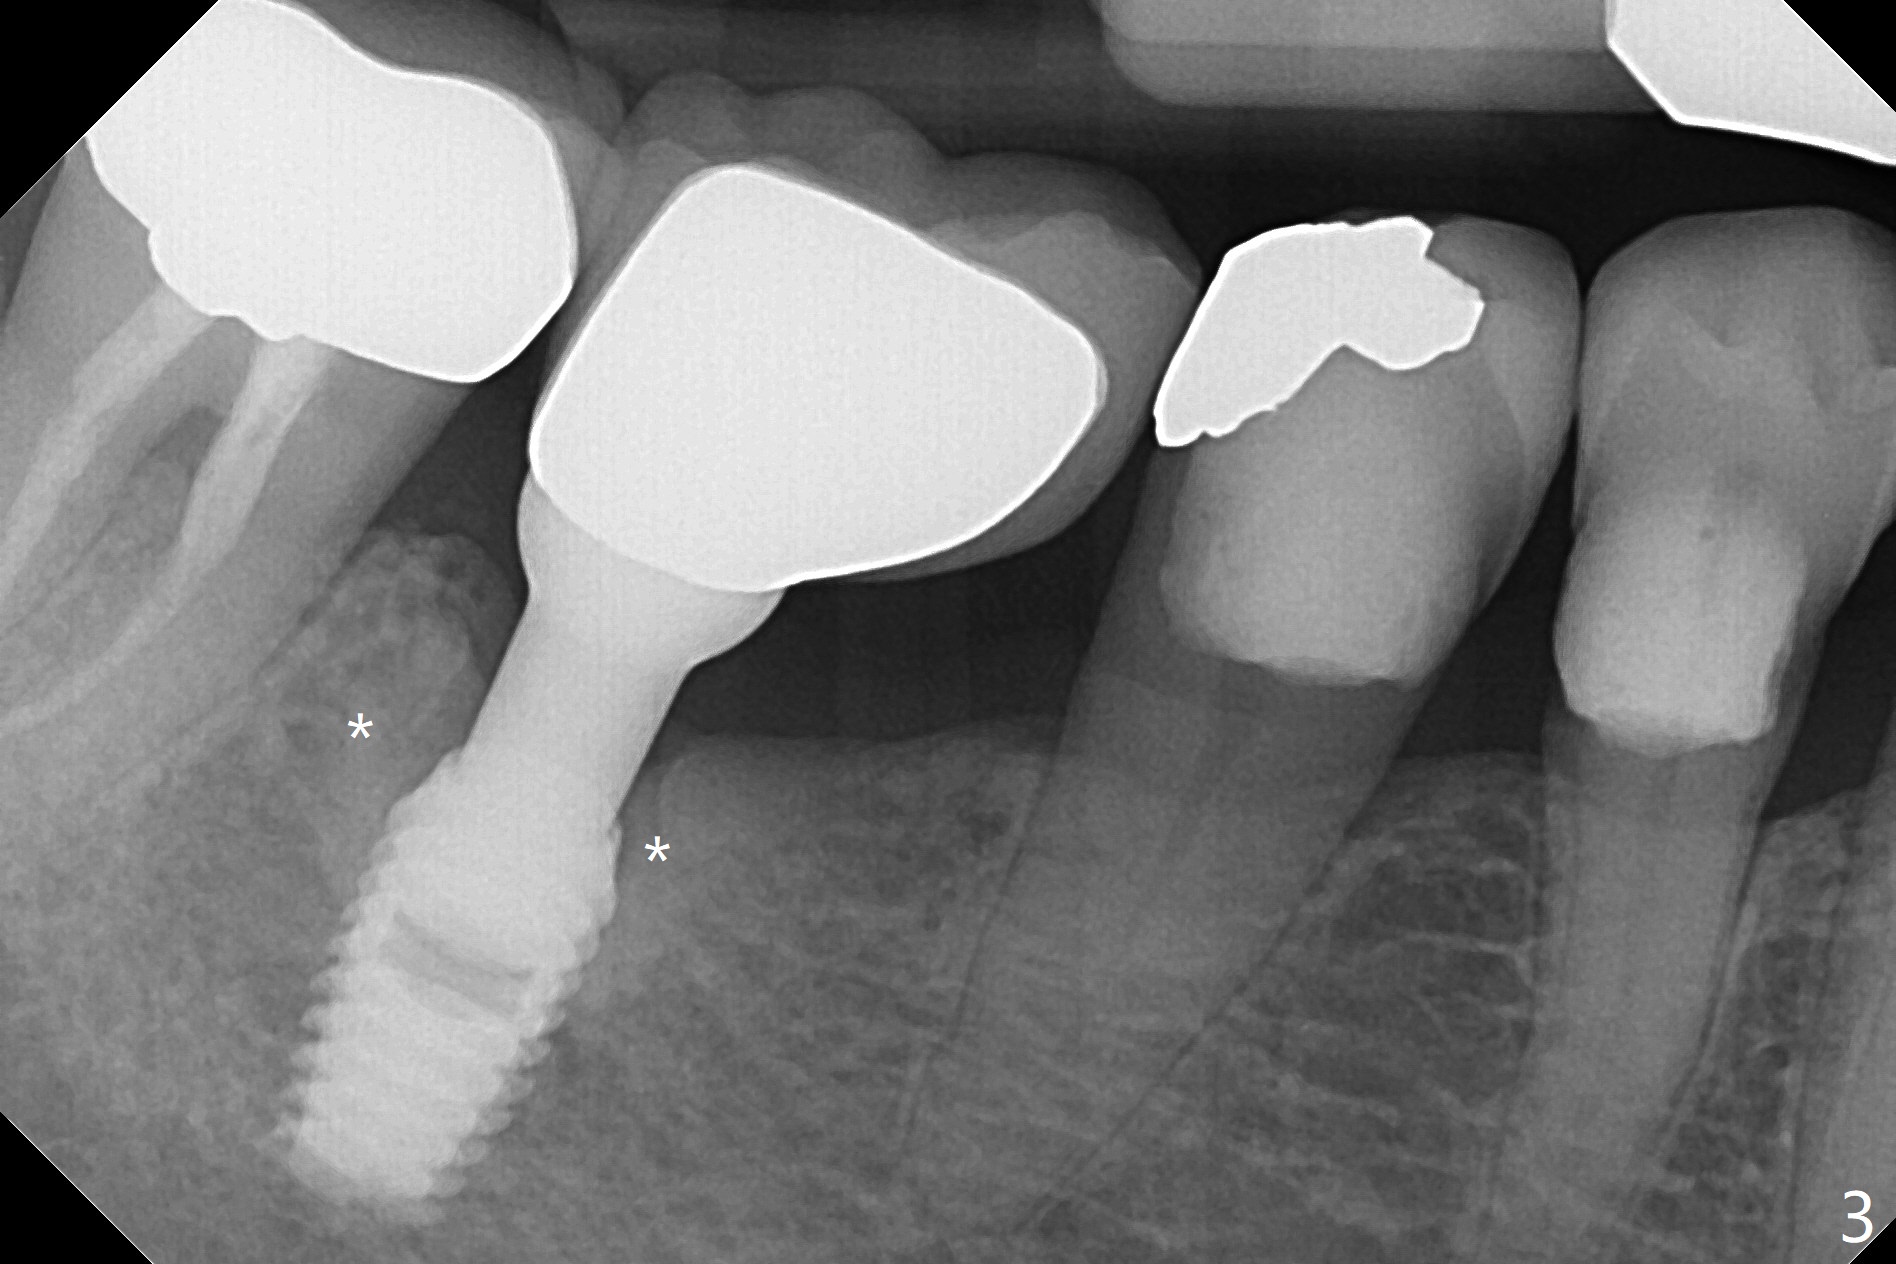

A 74-year-old woman with history of osteoporosis treatment had panoramic X-ray taken 7.5 years post cementation (Fig.2), eight years post Bicon implant placement (Fig.1). Bone density increases around the implant 9 years 7 months post cementation (Fig.3).